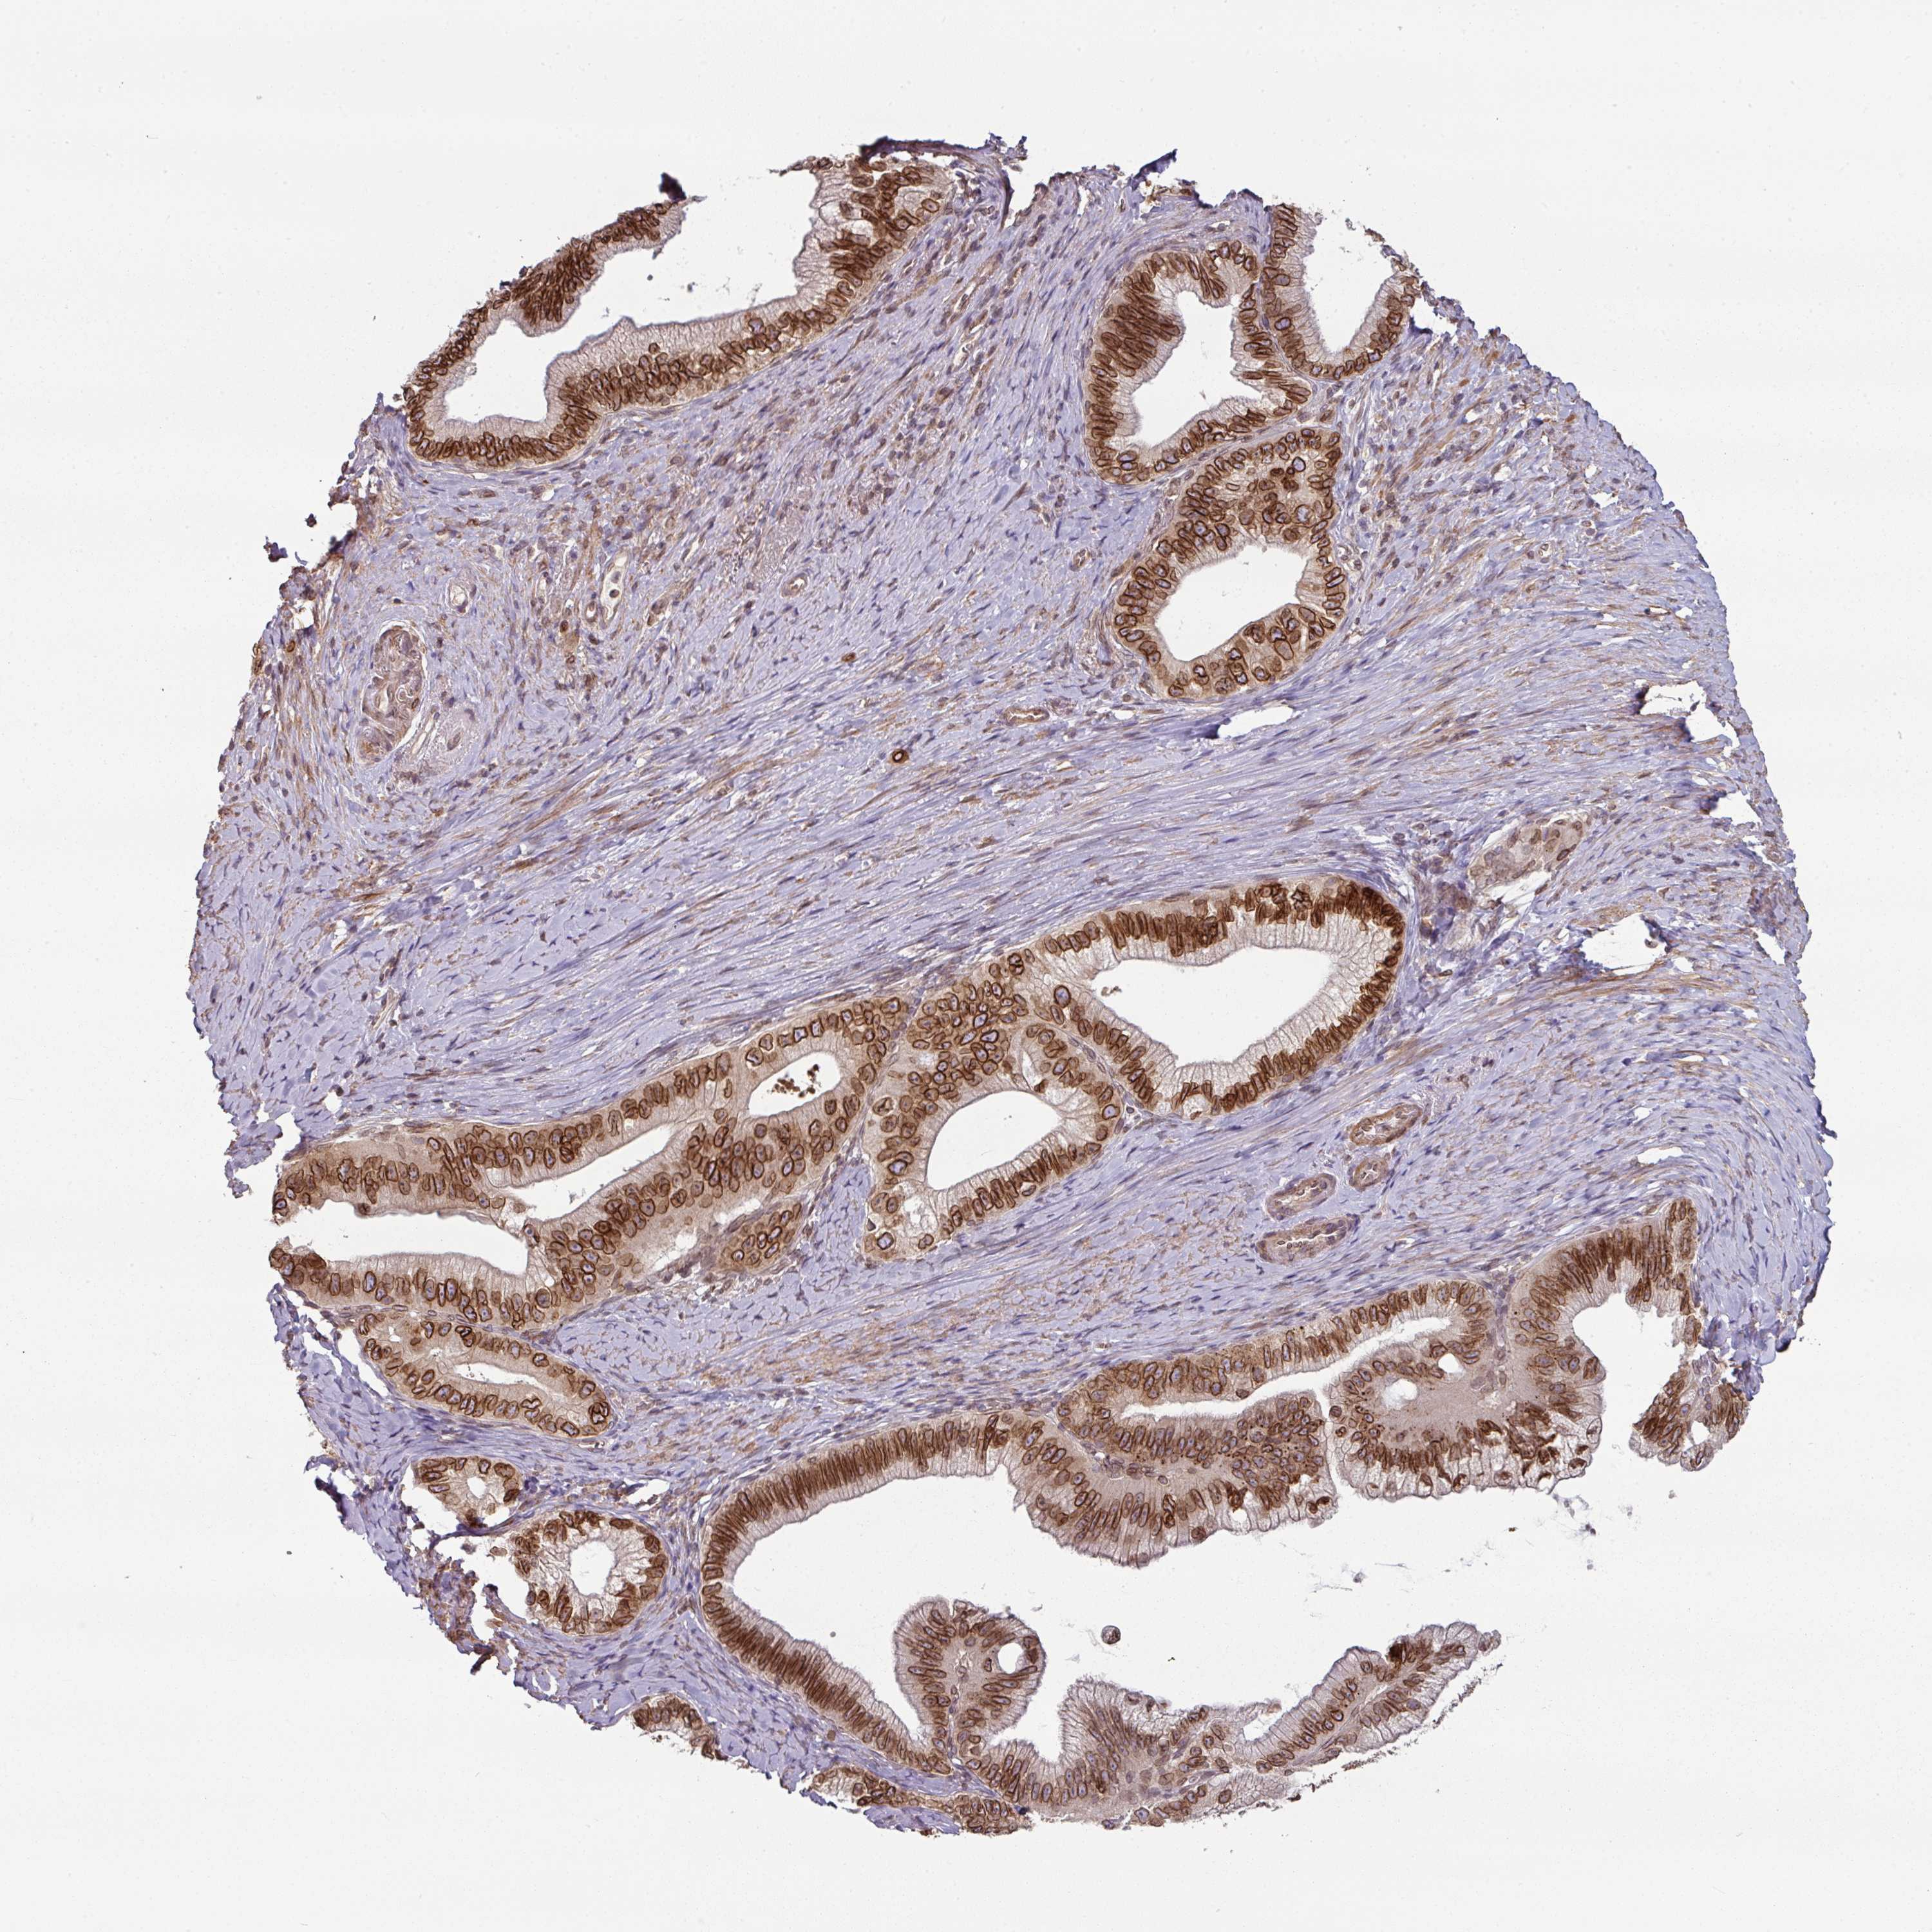

PANCREATIC CANCER - Protein expressioni

A mouse-over function shows sample information and annotation data. Click on an image to view it in a full screen mode. Samples can be filtered based on level of antibody staining by selecting one or several of the following categories: high, medium, low and not detected. The assay and annotation is described here.

Note that samples used for immunohistochemistry by the Human Protein Atlas do not correspond to samples in the TCGA dataset.

Antibody stainingi

Antibody staining in the annotated cell types in the current human tissue is reported as not detected, low, medium, or high, based on conventional immunohistochemistry profiling in selected tissues. This score is based on the combination of the staining intensity and fraction of stained cells.

Each image is clickable and will lead to virtual microscopy that enables deeper exploration of all samples and also displays staining intensity scores, fraction scores and subcellular localization as well as patient and tissue information for each sample.

Antibody HPA050110

Antibody CAB004293

Staining

High

Medium

Low

Not detected

Intensity

Strong

Moderate

Weak

Negative

Quantity

>75%

75%-25%

<25%

None

Location

Nuclear

Cytoplasmic/membranous

Cytoplasmic/membranous,nuclear

Adenocarcinoma, metastatic, NOS